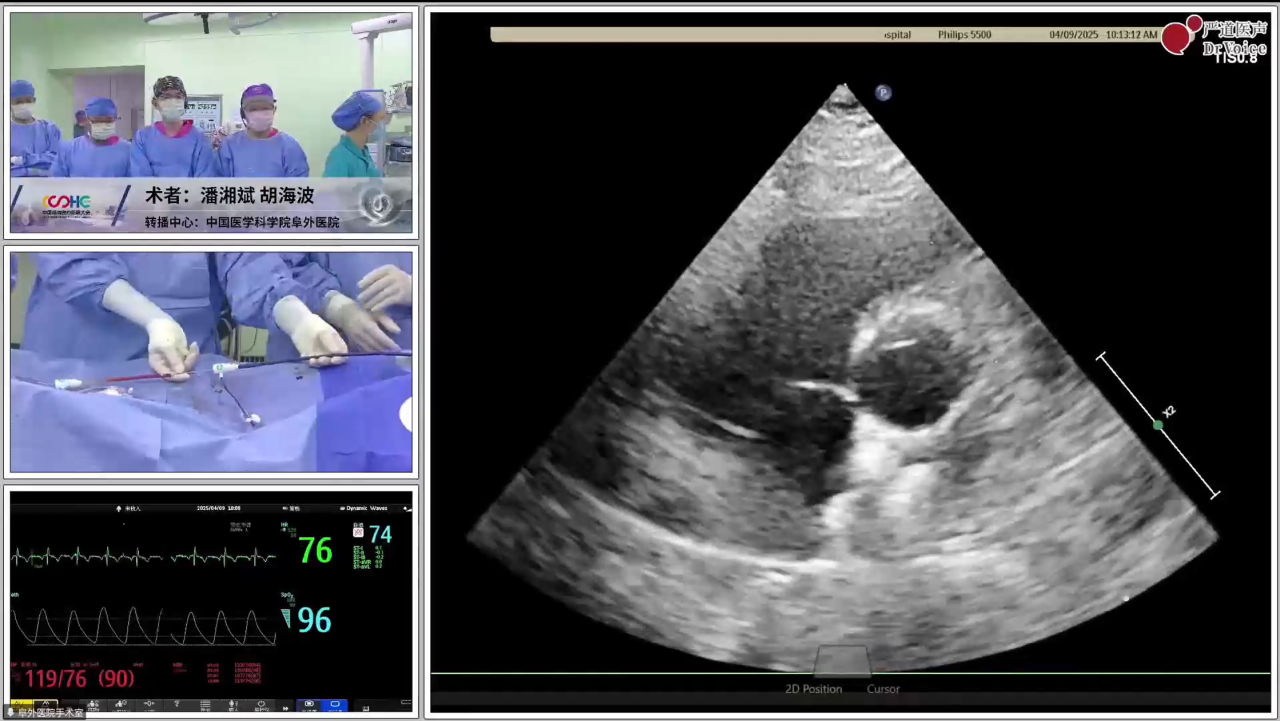

实战示教:中国医学科学院阜外医院结构性心脏病团队——两例单纯TTE引导下可降解PFO封堵术

左:第一例手术录播、右:第二例手术直播

第一例患者较年轻,有脑梗史,反复头痛数年,经食道发泡试验阳性,提示存在PFO。第二例患者39岁,偏头痛10余年,头颅核磁提示多发缺血灶,食道超声证实PFO,宽约2.4 mm、长约8 mm。两例患者均具备封堵指征,结合患者意愿,经术前充分检查后拟行单纯TTE引导下可降解PFO封堵,分别植入对称型24 mm*24 mm可降解PFO封堵器、对称型24 mm*24 mm可降解PFO封堵器。

为减少大鞘在心房内停留时间,可提前装载封堵器。两例手术均在单纯超声指导下开展,第二例患者术中通过导管配合超声导丝法顺利过隔,第一例患者经导管导丝探查法尝试过隔未果后,改用鞘管配合导丝法。术中所采用的PannaWire超声专用导丝为两例手术的新利器,其头端呈梭型,超声很容易探测,具有较佳的指向性,既降低了过隔难度,又提升了操作安全性。对于第一例患者,经超声确认导丝头端位于卵圆窝附近后,保持鞘管头端垂直指向房间隔方向缓慢推送,待导丝头端影像消失即提示鞘管已成功贴靠卵圆窝,后在其支撑下,导丝顺利过隔,建立股静脉至左心房的导丝轨道。

完成导丝轨道建立后,置入输送鞘。封堵器经鞘顺利送入左房后,在超声引导下先释放左盘面,通过牵拉成型线使其由“灯笼状”变为“盘状”,再回撤钢缆,使左盘紧贴房间隔。待右盘面释放后牵拉成型线,若超声下观察到右盘随房间隔摆动,且双盘贴合于间隔、形态合适,即开始锁定。成型锁定后,超声下双盘面紧紧扣合在房间隔两侧,形态良好,且轻轻牵拉钢缆,双盘相对位置保持不变,依然紧贴合房间隔,判定锁定成功。

锁定后牵拉测试—左:第一例、右:第二例

术后超声—左:第一例、右:第二例